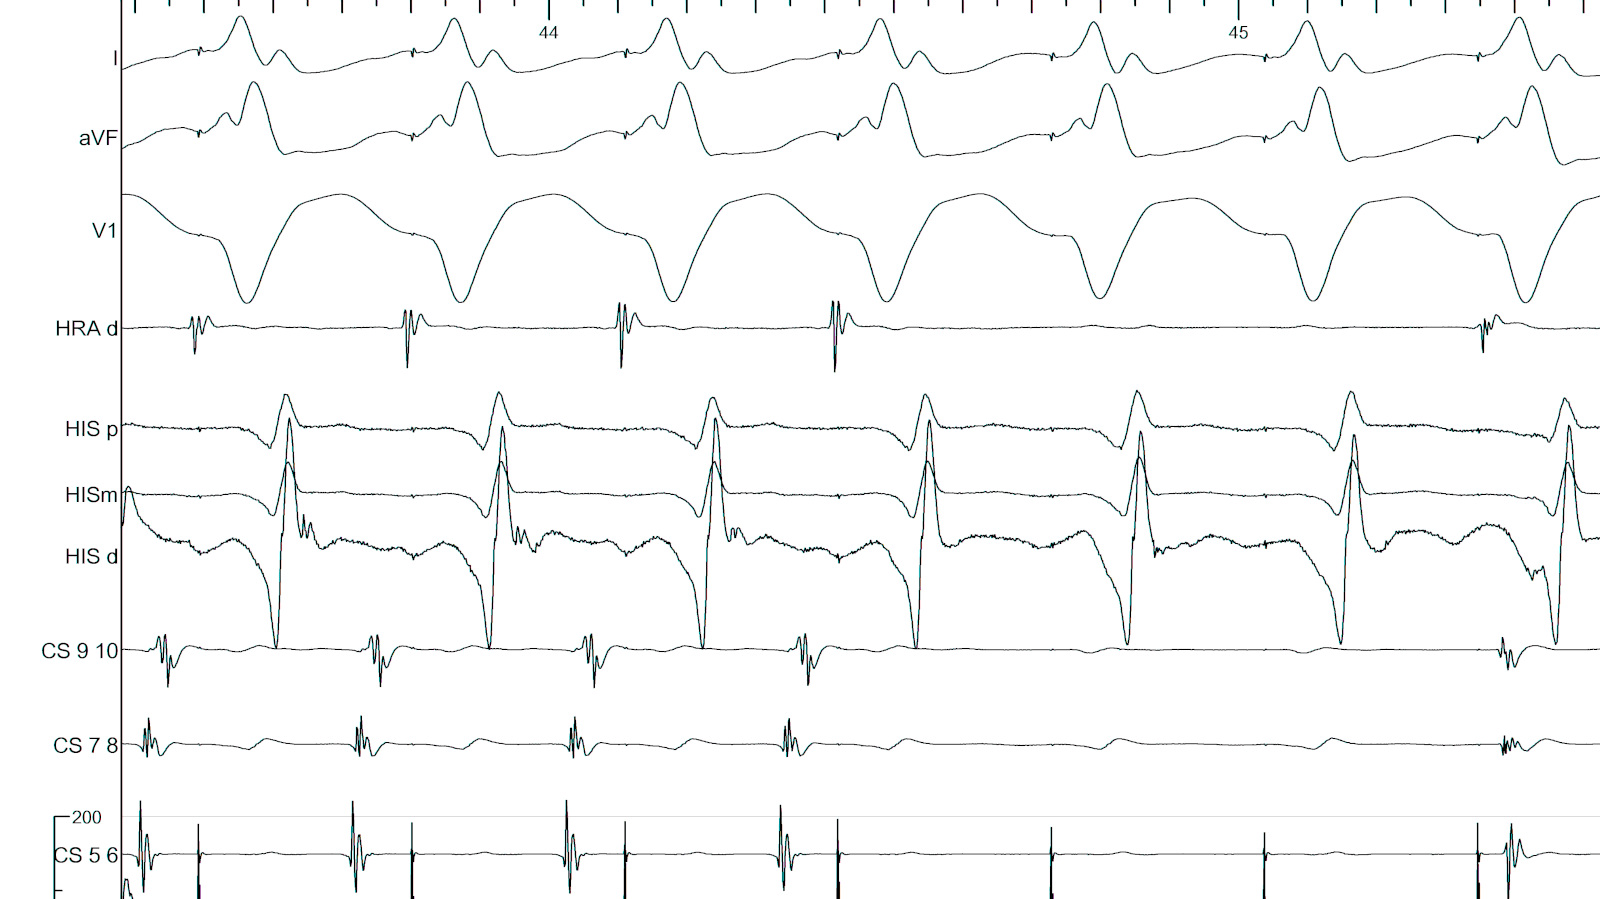

Use triggered mode

trigger.jpg